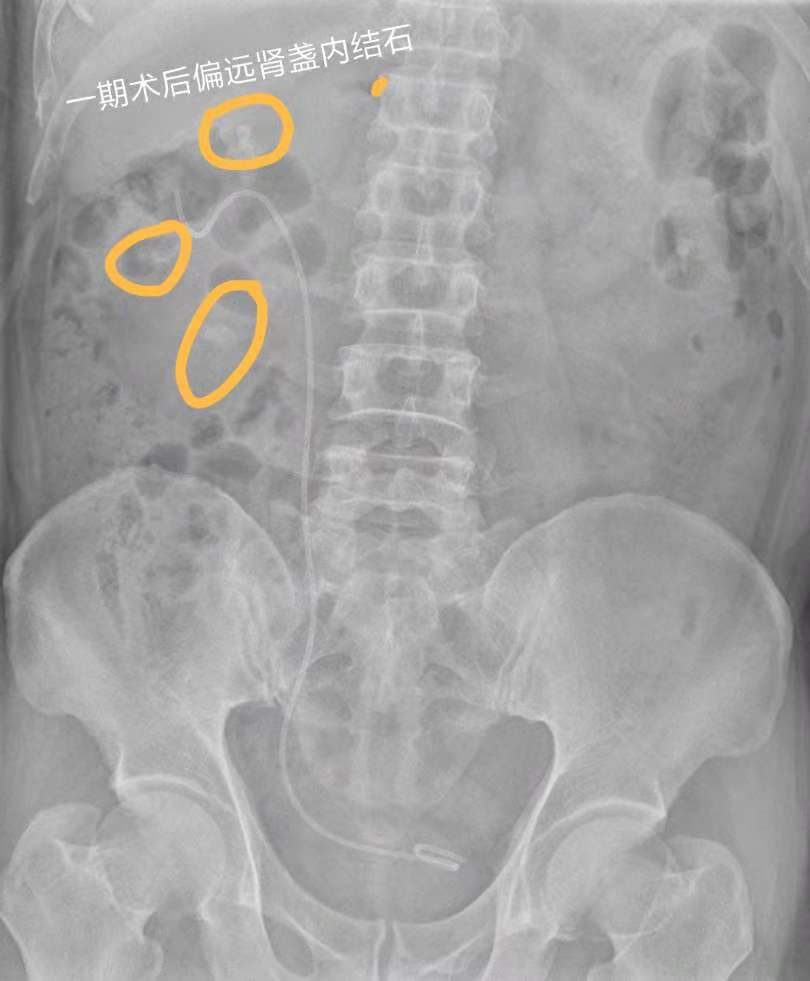

一期术后复查平片